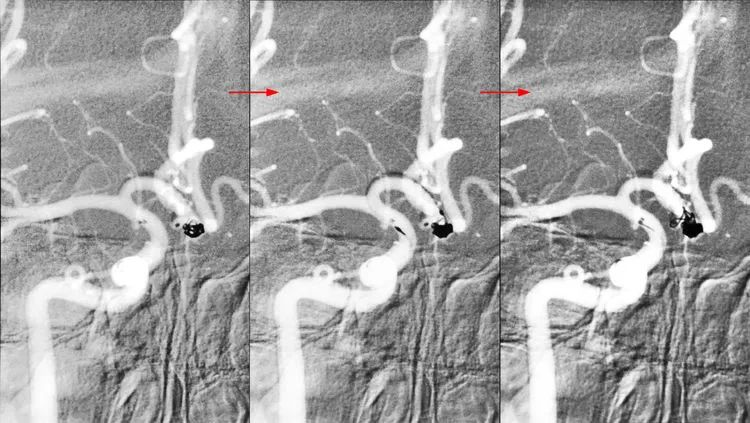

经甲管向大分叶内依次填入3枚弹簧圈(MicroPlex 10-3-6-Cosmos Complex,PC-3-6-3D,PC-3-4-3D),第3枚弹簧圈的一个环挤入小分叶: